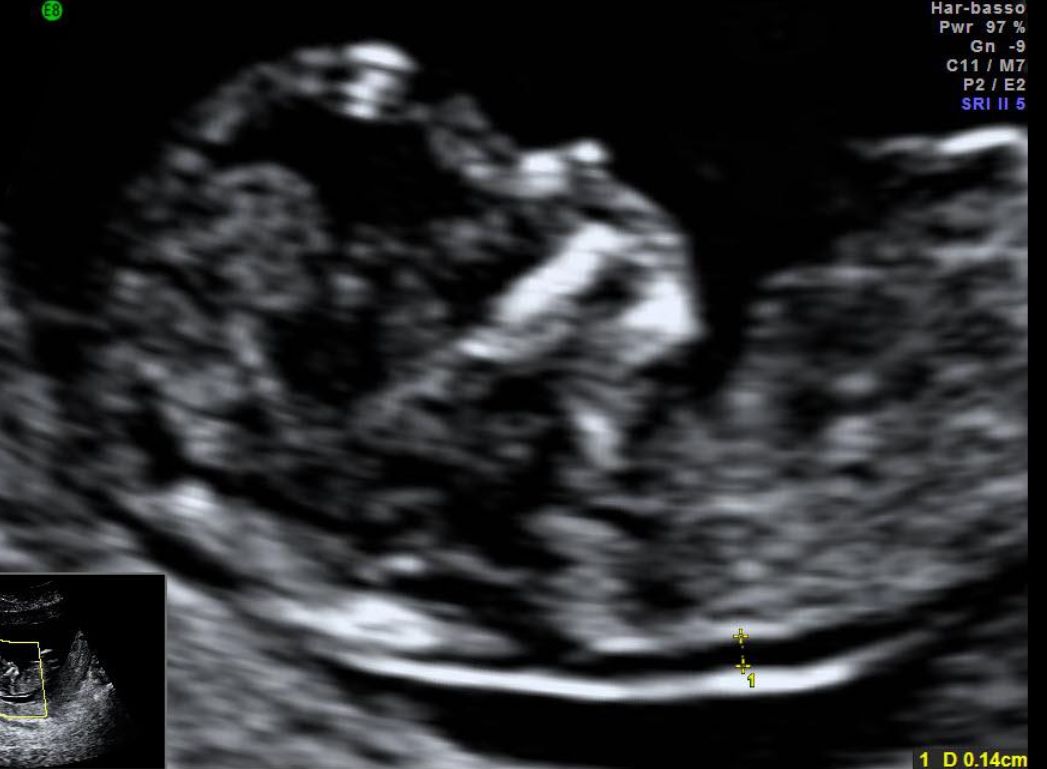

Eseguo visite ed ecografie ginecologiche, ecografie ostetriche del I trimestre , ecografie per la misurazione della translucenza nucale, ecografie ostetriche morfologiche e del III trimestre e visite ostetriche.